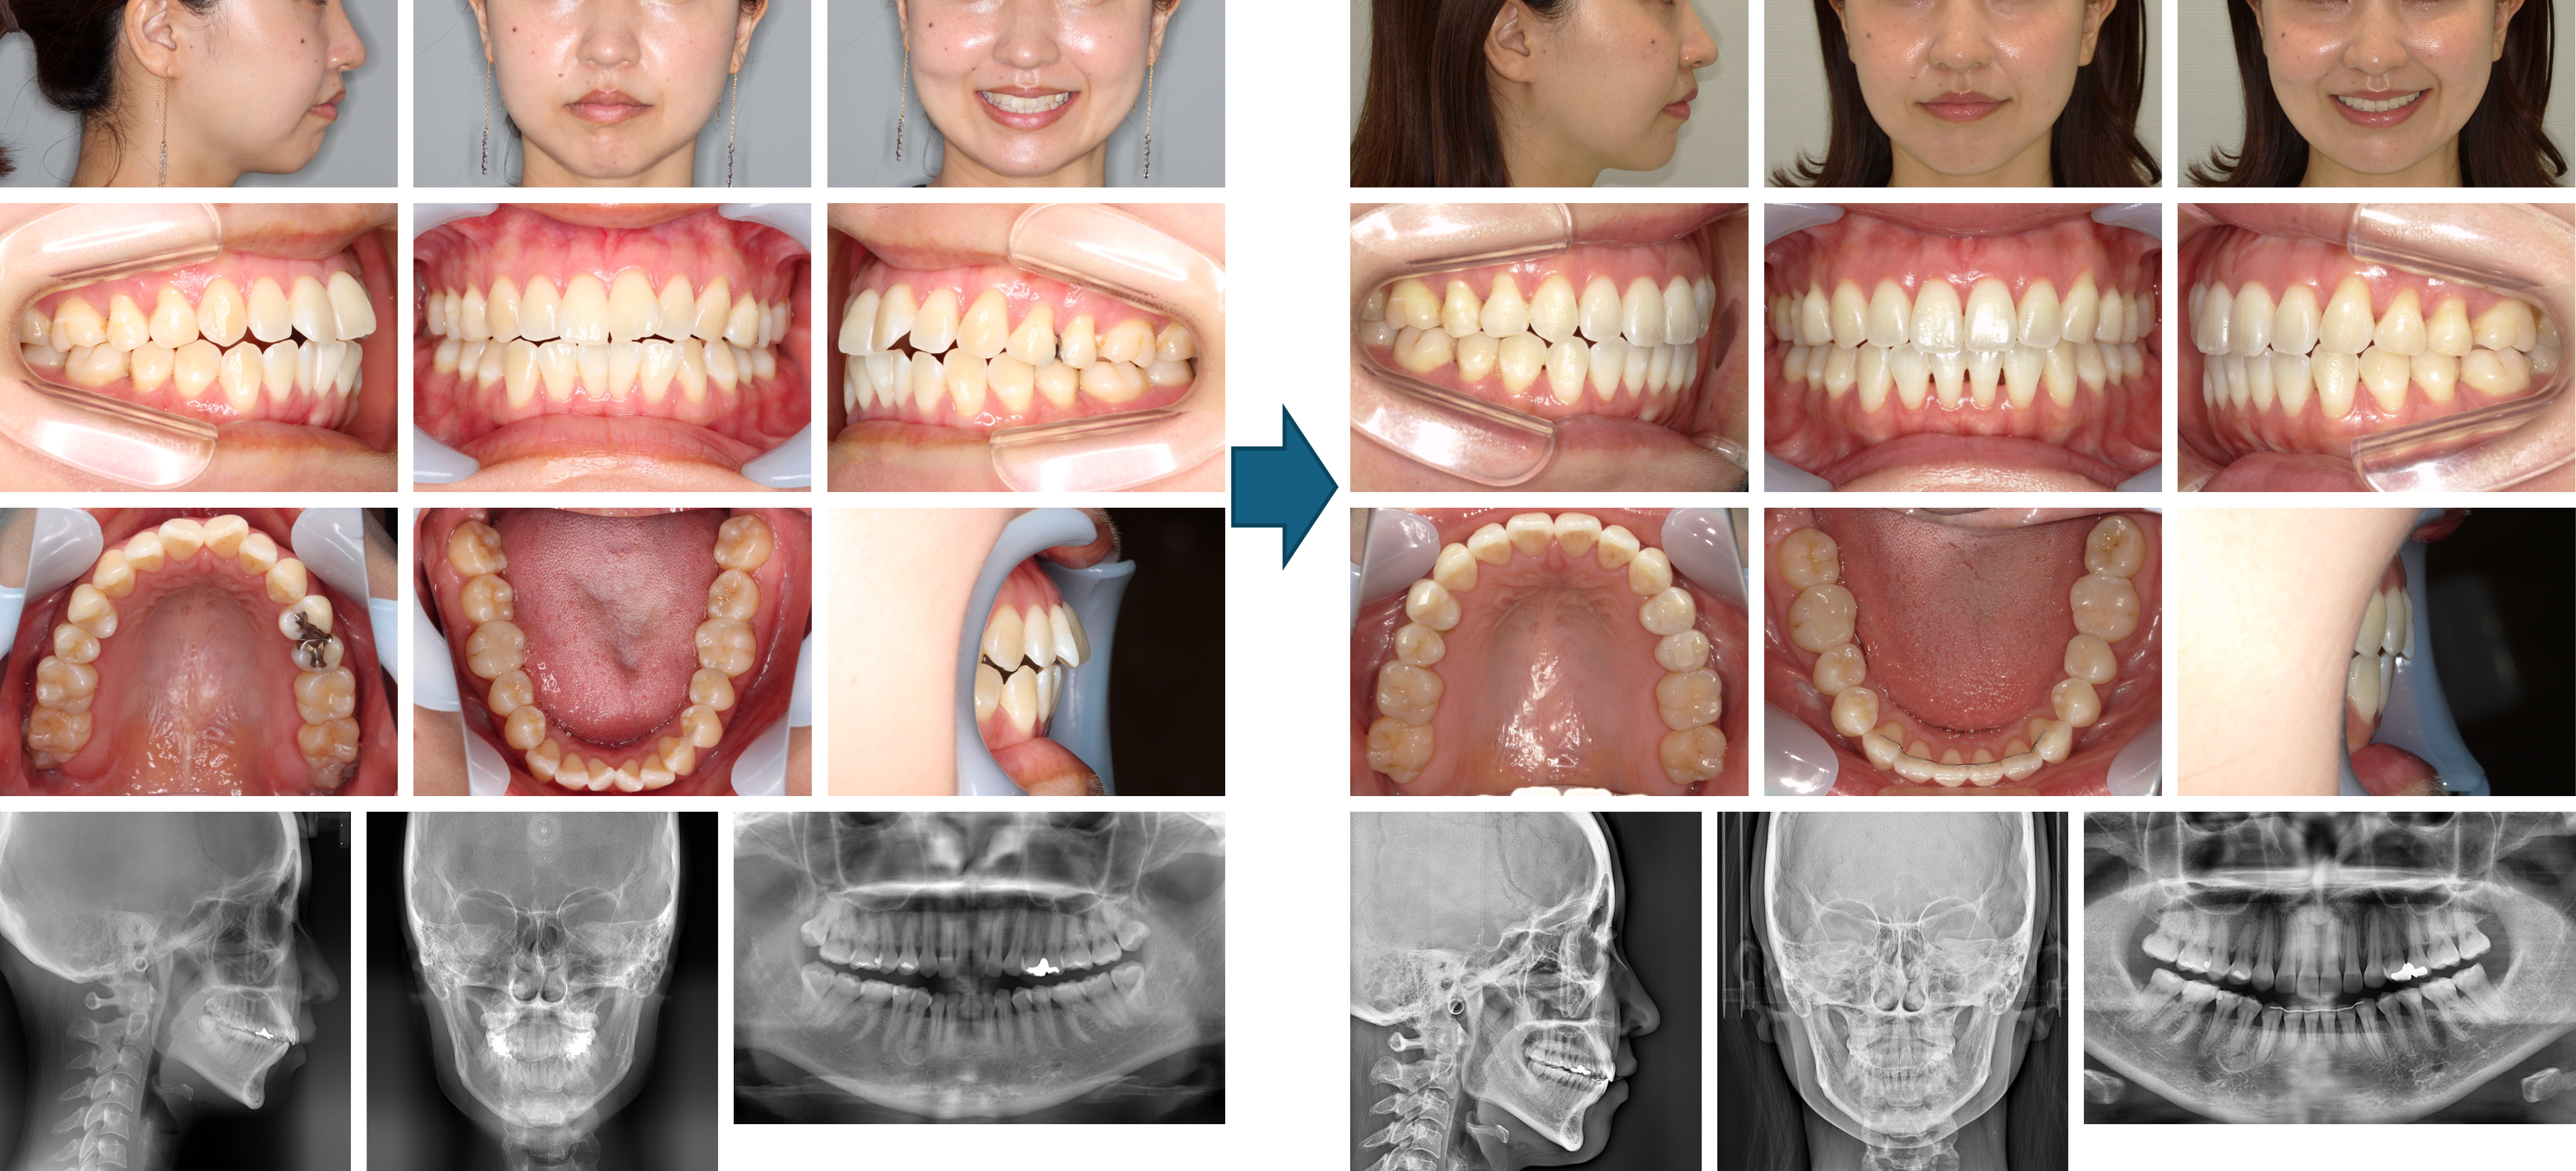

【治療例】初診時年齢:23歳4か月 / 性別:女性 / 主訴:上の歯が出てきた気がする、正中がずれている

症例の概要:この症例は、当院で幼少期にマルチブラケット装置にて治療を行ったが、成人になって上の前歯が出てきた気がするということで来院された。下顎の正中が顔面正中に対して左方偏位していることで左側の臼歯関係はⅡ級を呈した。マウスピース型(アライナー型)矯正装置(インビザライン®)でIPRを行いながら唇側傾斜の改善ならびに正中線の一致を試みた。その結果、左側の臼歯関係はⅠ級関係を築き、唇側傾斜の改善および正中線が一致した。

主訴:上の歯が出てきた気がする、正中がずれている

診断名: 左側アングルⅡ級の上顎前突症例

使用した主な装置: マウスピース型(アライナー型)矯正装置(インビザライン®)、IPR、顎間ゴム

抜歯/非抜歯および抜歯部位: 非抜歯

※こちらの症例は2023年5月から2024年12月に行った矯正歯科治療です(現在も経過観察中)

治療期間:1年7か月

治療回数:19回

リスクの副作用:歯の移動や抜歯による違和感や疼痛、口内炎、歯肉退縮、歯根吸収が生じることがある